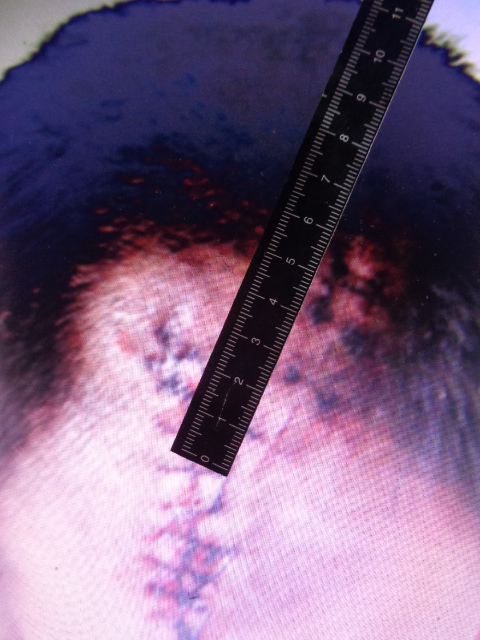

被鉴定人周某损伤部位及CT影像

二条头皮锐器创痕,分别长约9cm、9cm